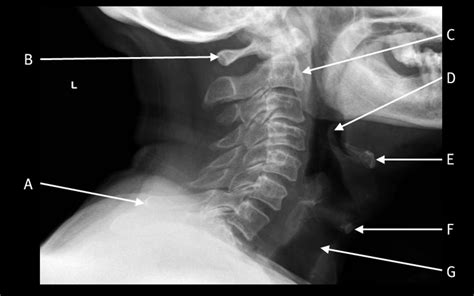

Interpreting a Normal Neck X Ray

Interpreting a Normal Neck X Ray involves examining the images for any abnormalities. Key structures to assess include:

• Vertebrae: The seven cervical vertebrae (C1-C7) should be clearly visible and aligned.

• Intervertebral Discs: The spaces between the vertebrae should be uniform and without narrowing.

• Joints: The facet joints should be well-defined and without signs of degeneration or inflammation.

• Soft Tissues: The soft tissues, including muscles and ligaments, should appear normal without any swelling or masses.

• neck x ray anatomy